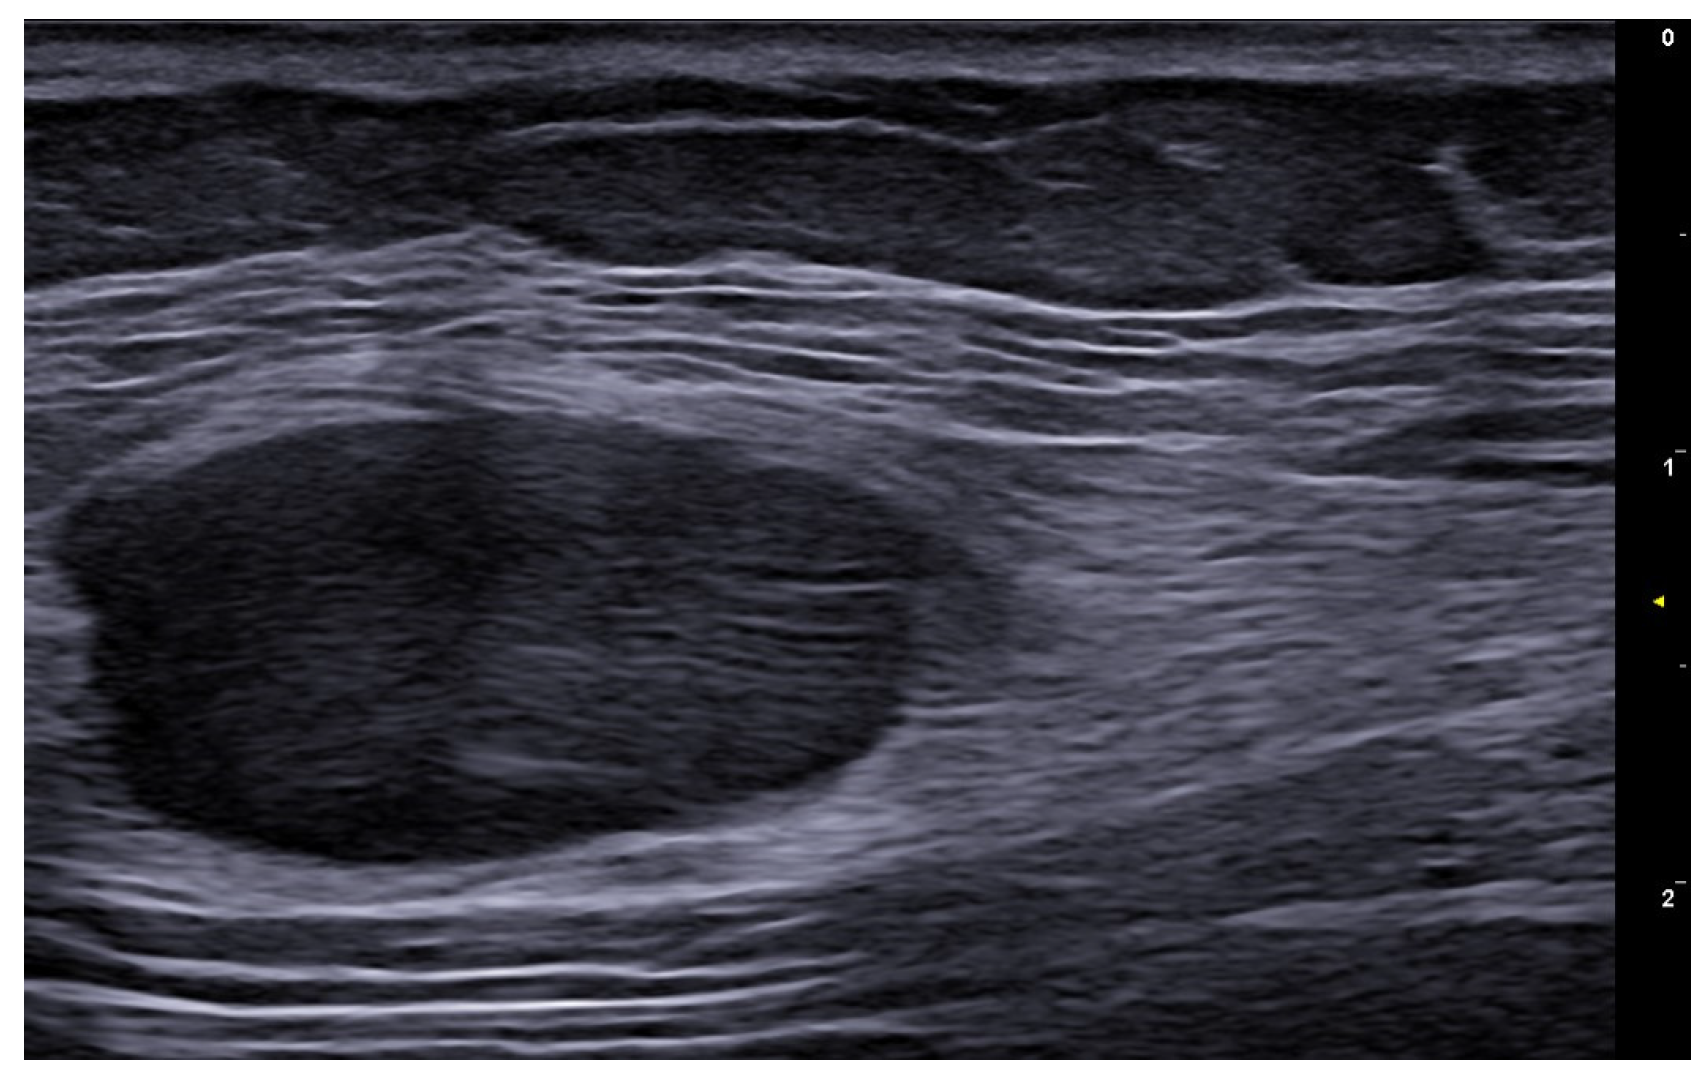

7. External-Agent-Associated Disorders

8. Neoplastic Diseases